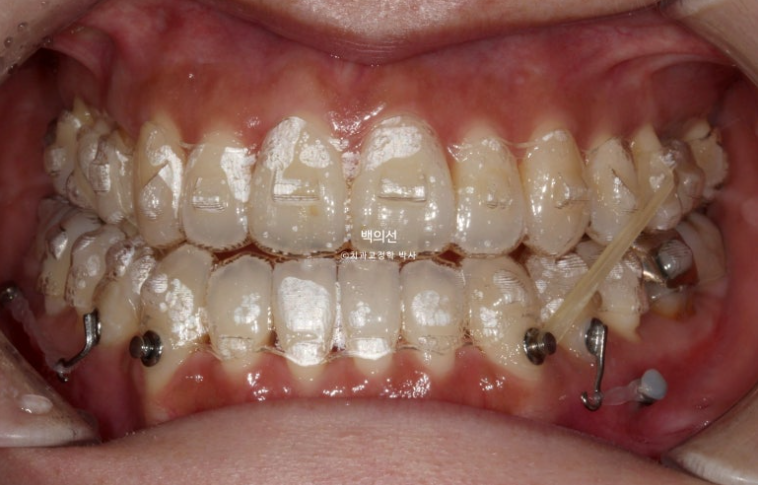

24.11

첫세트의 장치는 45개가 나왔습니다.

아래에는 교정용 나사인 미니스크류를 양쪽 1개씩 심고 환자가 스스로 뺏다 꼈다 하는 악간고무줄 처방도 같이 들어갑니다.

11개월에 걸쳐서 장치를 모두 낀 후 모습입니다.

앞니 반대교합은 해소가 되었고 아래 앞니 배열이 개선되면서 생긴 블랙트라이앵글이 보입니다.

아직은 어금니가 뜨고 교합이 잘 안되는 상태입니다.

미니스크류와 연결된 작은어금니의 회전을 바로 잡기 위해 안쪽에도 고무줄 고리가 붙어있습니다.